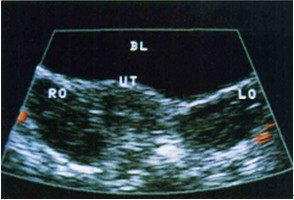

卵巢外形呈扁椭圆形,边界稍有凹凸,中央部为髓质,回声略高。周围区为皮质,回声略低,其内可显示大小不等、边清壁薄的圆形液性暗区为卵泡回声(见图1)。

图1 正常卵巢(箭头所指)